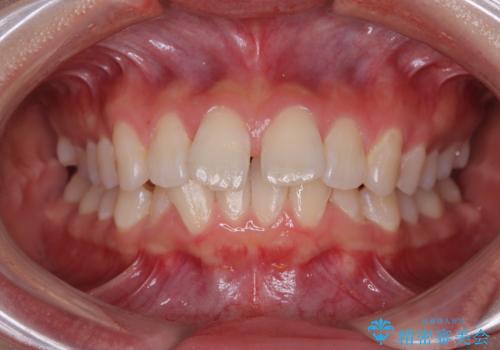

骨格性のディープバイト 補助装置を併用したワイヤー矯正治療で咬み合わせを改善